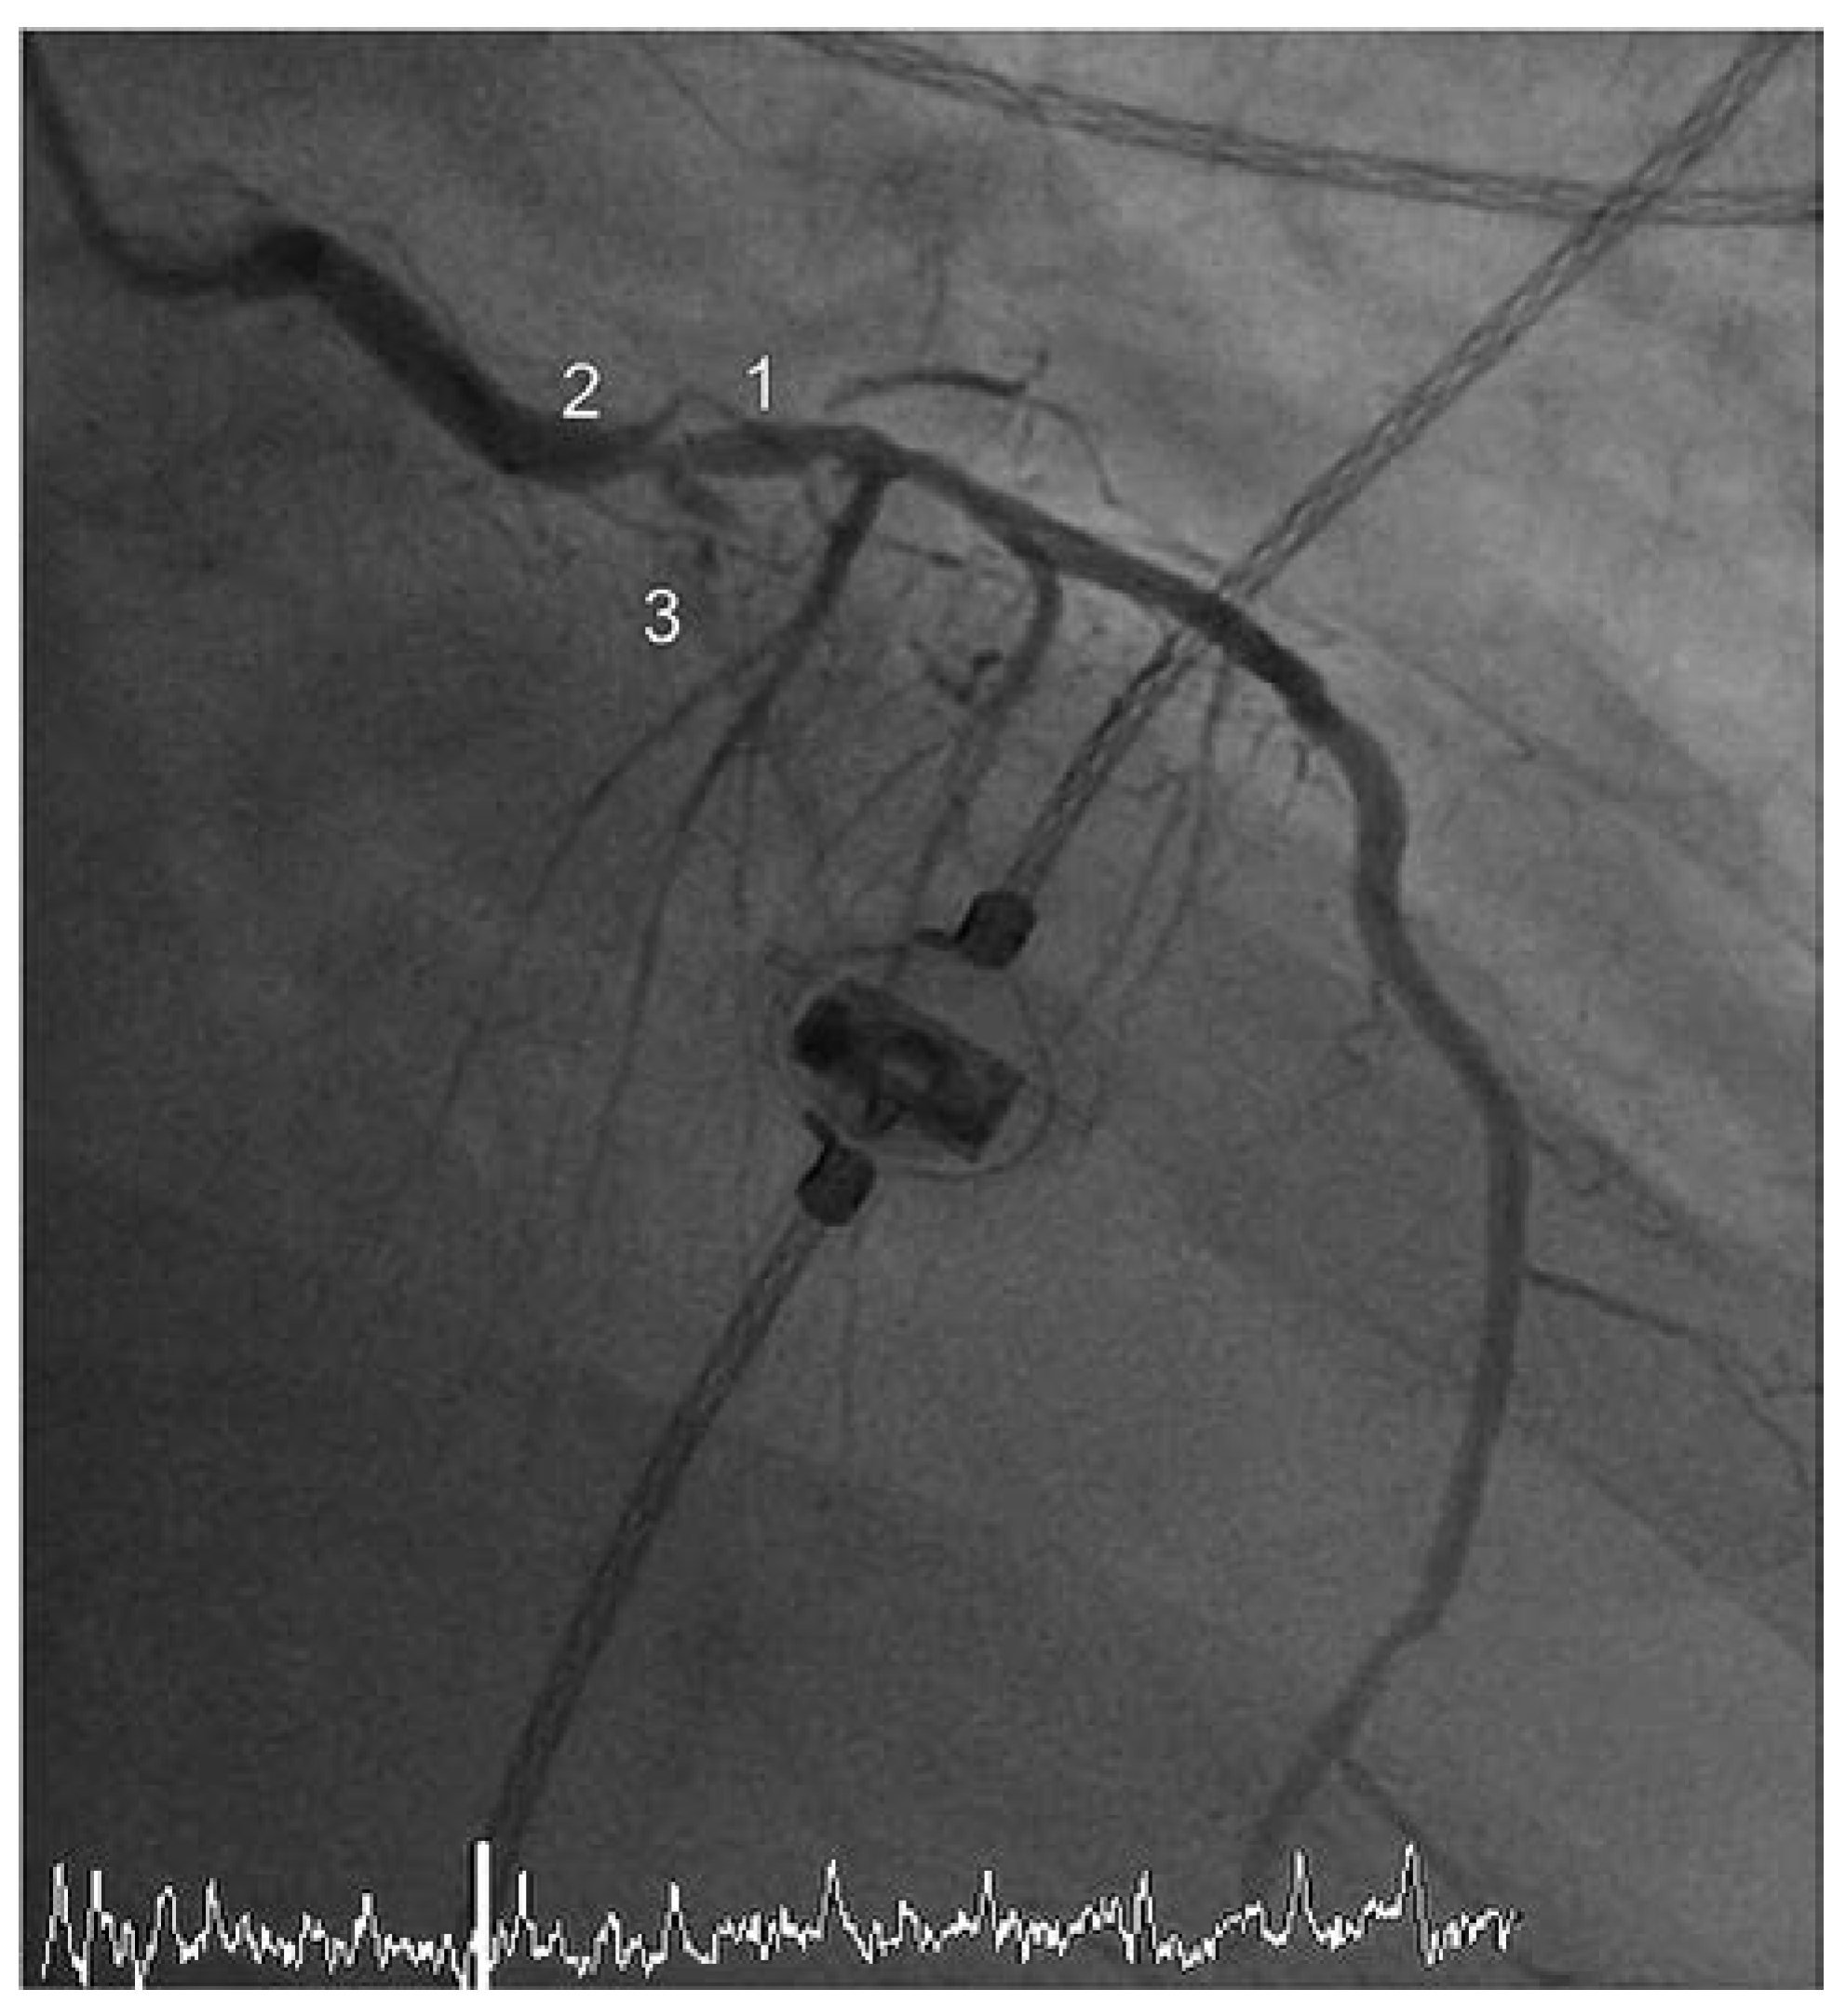

Die Zuweisung des 90-jährigen Patienten durch die Sanität erfolgte aufgrund eines akuten anterioren ST-Hebungsinfarktes mit typischer Symptomatik und zweifach über der Norm erhöhtem hoch-sensitivem Troponin T. Die Koronarangiographie zeigte als ursächliche Läsion einen Verschluss des mittleren Ramus interventricularis anterior (RIVA) (Abbildung 1). Insgesamt fand sich angiographisch eine schwerere koronare 3-Gefäss-Erkrankung: 70% Hauptstammstenose, mittlerer RIVA-Verschluss, subtotale Stenose des Ramus intermedius (RIM), 70% Stenose des 1. Marginalastes des Ramus circumflexus (RCX) und ein chronischer Verschluss der rechten Koronararterie (RCA). Ventrikulographisch zeigte sich eine schwer eingeschränkte linksventrikuläre systolische Funktion (Auswurffraktion [EF] = 25%) bei Akinesie der Vorderwand sowie Hypokinesie der übrigen definierten Segmente.

Abbildung 1. Koronarangiographie vor Intervention – Fall 1. 1 – RIVA, 2 – Hauptstamm, 3 – RIM, 4 – Marginalast 1/RCX. 5 – retrograde Darstellung der chronisch verschlossenen RCA.

Unter diesem hämodynamischen Backup gelang die Durchführung der PCI mit Rekanalisation des RIVA mittels PTCA und 3-fach-Stent-Implantation (3× «drug eluting» Stents [DES]) sowie die Wiedereröffnung der subtotalen Stenose des Intermediärastes (PTCA/1× DES). Zudem konnte die hochgradige Hauptstammstenose mittels primärer Stentimplantation (1× DES) versorgt werden. Die Kontrollangiographie dokumentierte ein gutes postinterventionelles Ergebnis mit promptem Fluss bis in die Peripherie (Thrombolysis in myocardial Infarction-Klassifikation [TIMI] III) (Abbildung 2). Der Verschluss des arteriellen inguinalen Zugangs erfolgte mittels eines herkömmlichen perkutanen Verschluss-Systems (Angio-SealTM, St. Jude Medical, MN, USA).

Abbildung 2. Koronarangiographie nach Intervention – Fall 1.